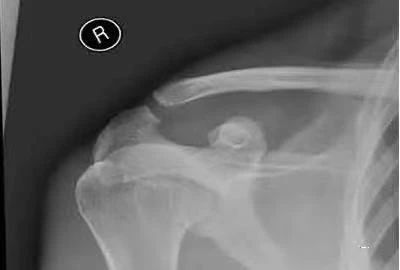

(3)肱骨大结节骨折肩关节前脱位:受伤机制与本病相近,也表现为肩部肿痛,活动受限,但有方肩畸形,可扪及异位肱骨头,肩关节弹性固定,有时两者常合并存在。

肩峰骨折:均为肩部肿痛,但压痛点位于肩峰部,被动外展时可有一定的活动度;X线片可见肩峰骨折。